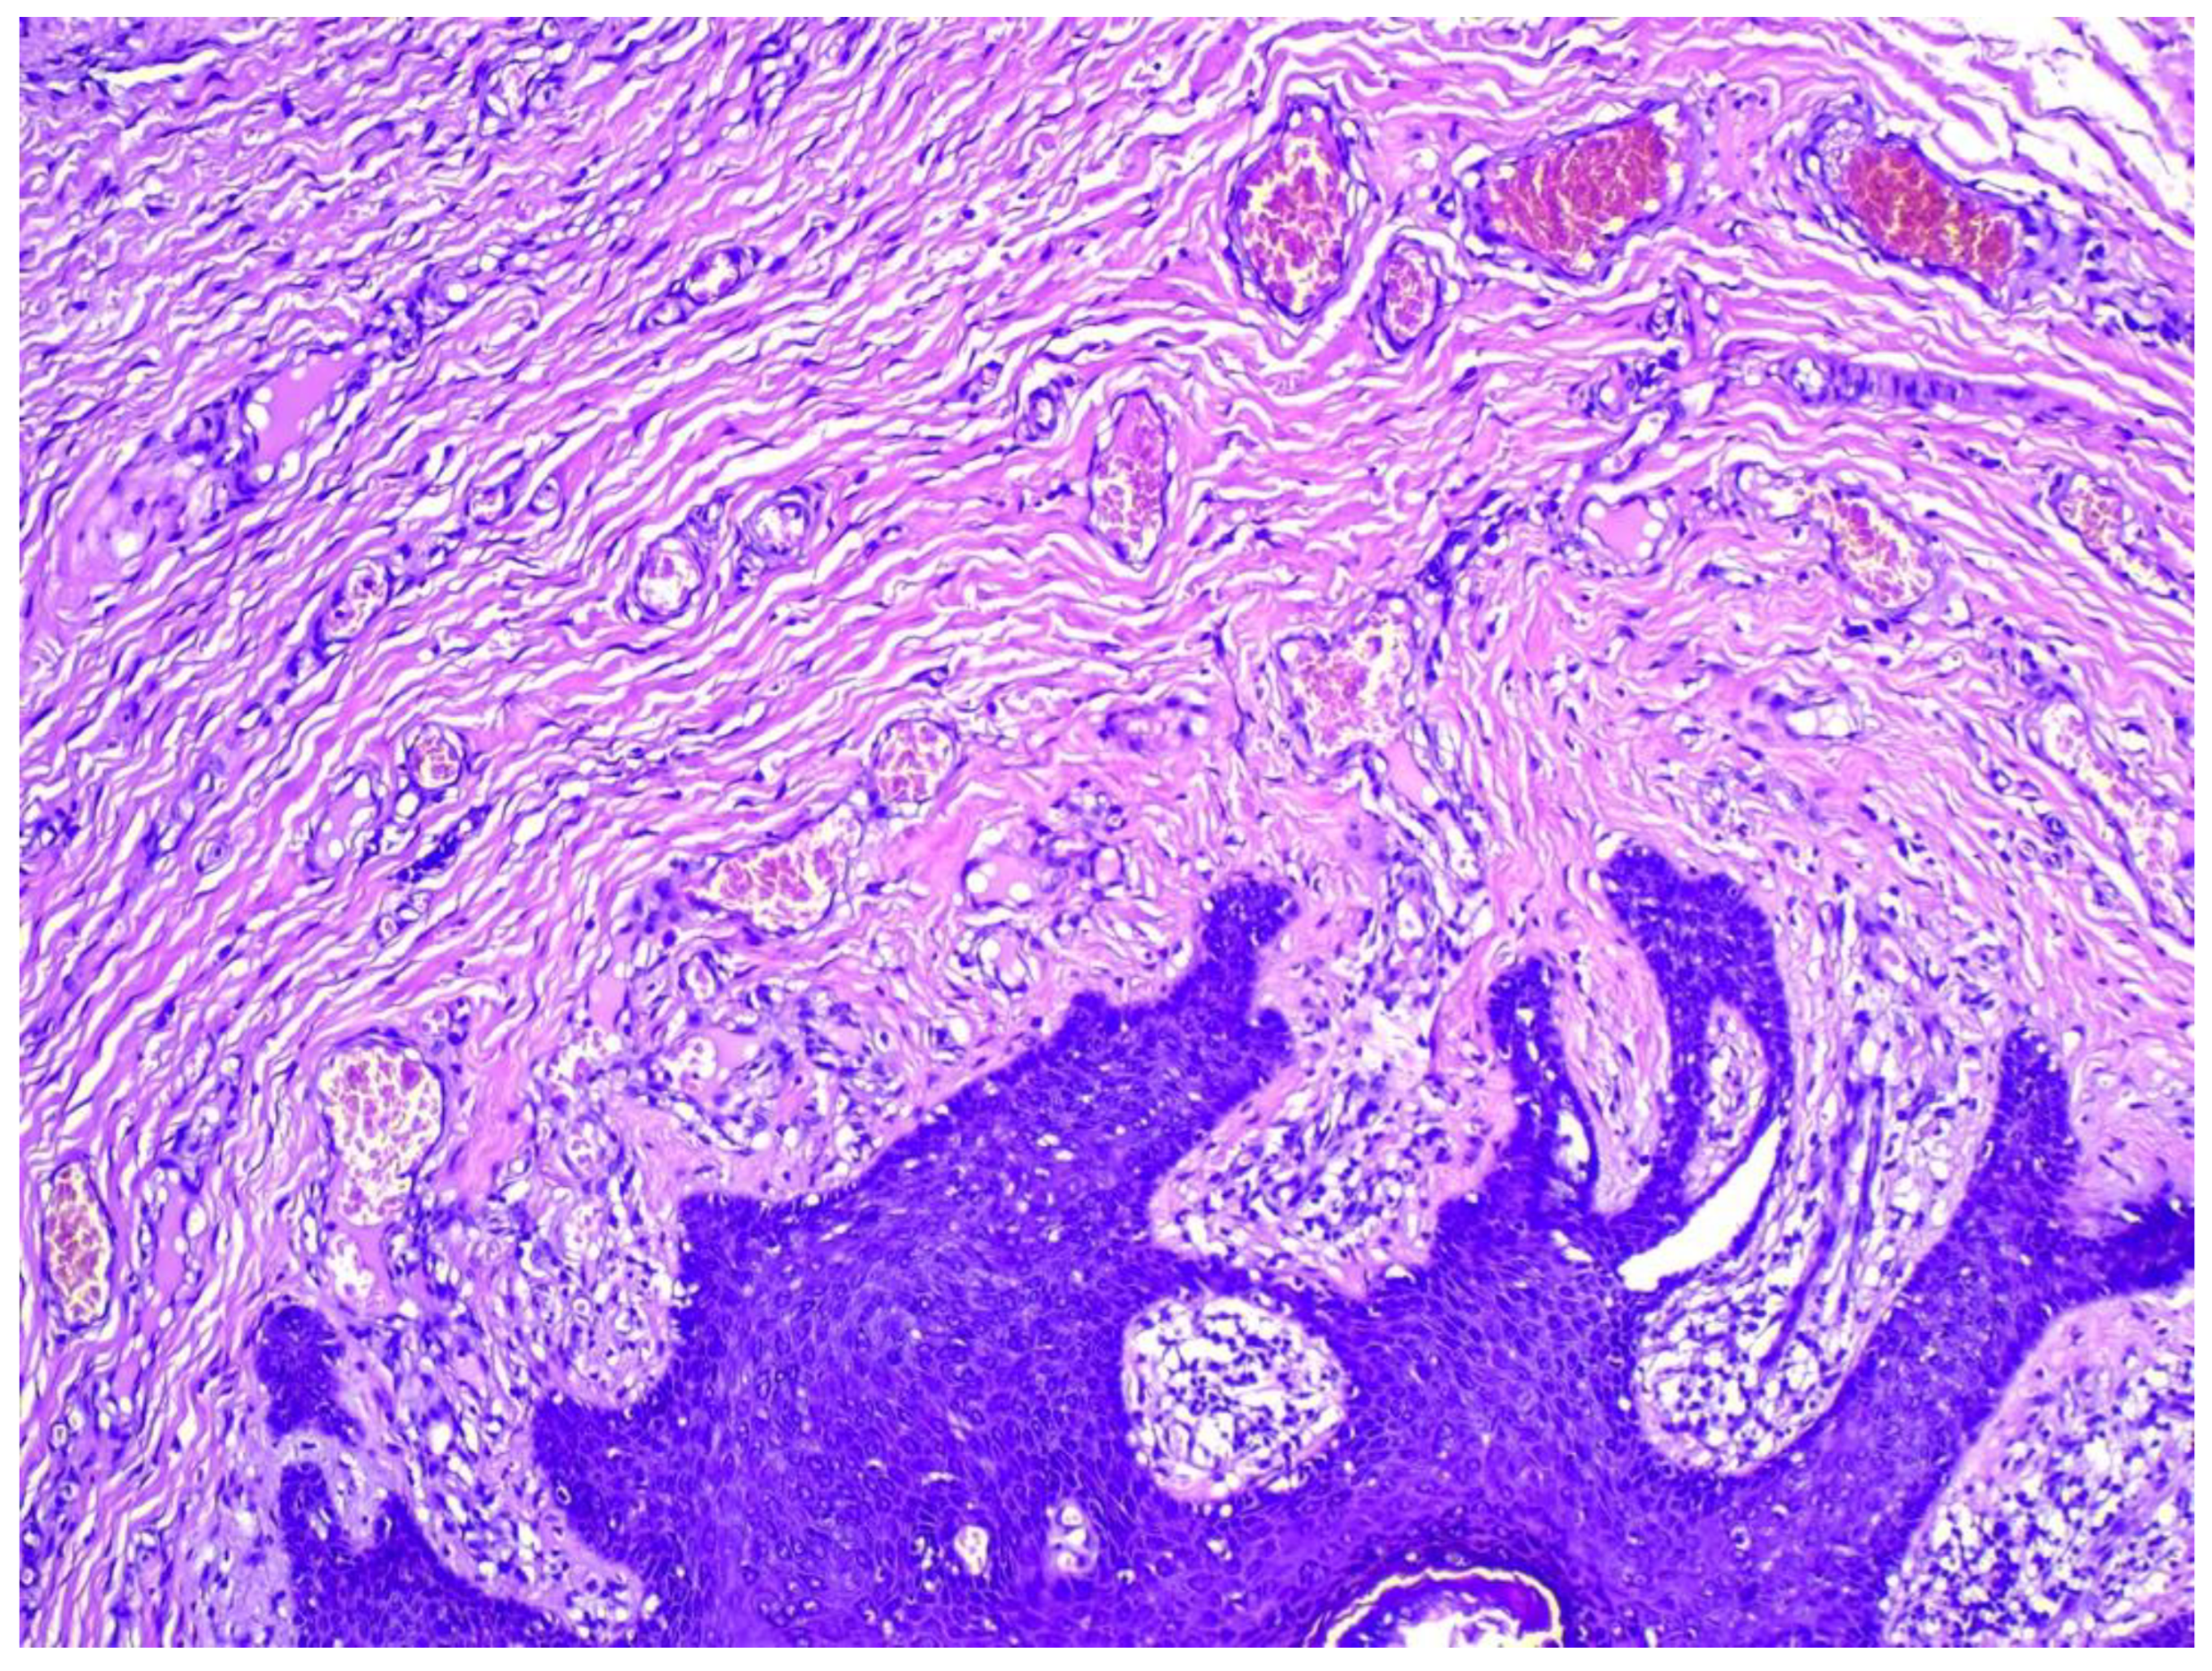

2. Detailed Case Description